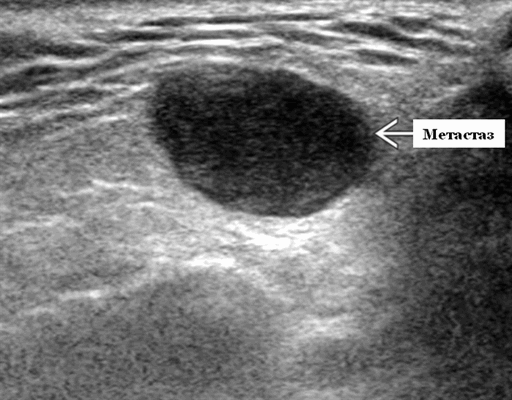

Метастазы в слюнную железу на УЗИ

Метастаз в поднижнечелюстной слюнной железе при ультрасонографии

Ключевые факты. Терминология. Гематогенное распространение раковых клеток на поднижнечелюстные железы

Данные УЗИ слюнной железы. Результаты визуализации метастазов поднижнечелюстных желез при ультразвуковом сканировании неспецифичны и имеют общие черты с другими злокачественными новообразованиями поднижнечелюстных желез.

- На УЗИ слюнной железы метастаз чаще всего выглядит как нечеткая сплошная масса.

- Гипоэхогенный по отношению к подчелюстной железе, изоэхогенный до умеренно гиперэхогенный по отношению к мышцам.

- ± кистозный компонент, представляющий внутренний некроз

- ± экстрагландулярное распространение, вовлечение прилегающих структур

- ± соседние лимфатические узлы поднижнечелюстного пространства

- Выраженная внутриузловая гиперваскуляризация.

Общие особенности при ультразвуковом сканировании слюнной железы

Лучший диагностический признак. Особенности визуализации неспецифичны. Чаще всего проявляется как нечеткое твердое гипоэхогенное образование ± внутренний некроз. Внутриузловая васкуляризация / гетерогенное усиление

Результаты ультразвукового исследования

Серошкальное УЗИ. Нечеткая солидная опухоль. Гипоэхогенная структура по отношению к подчелюстной железе, изоэхогенная / слегка гиперэхогенная по отношению к мышцам ± кистозный компонент, представляющий внутренний некроз ± экстрагландулярное распространение, вовлечение прилегающих структур таких как платизмальная мышца, подкожная клетчатка; подъязычно-подъязычные, подъязычные, двубрюшные мышцы; лицевая артерия, ретромандибулярная вена ± ипсилатеральное поднижнечелюстное пространство, шейные лимфатические узлы